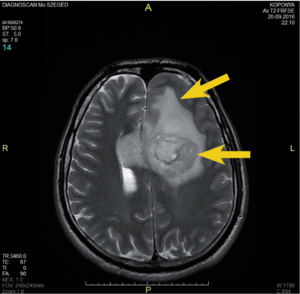

3.6.2. Daganatok: az agy (64–72. ábra)

- MRI: T2, FLAIR, T1/T1gad, DWI.